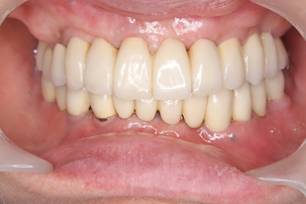

術後。上部構造はハイブリッドレジンです。しっかり嚙めるようになり喜んでいただきました。

上顎

下顎

上部構造装着後6年。ハイブリッドレジンを使用したため、少し艶がなくなってきました。上部構造の材料には金属、ハイブリッドレジン、セラミックなどがあります。セラミックはきれいですが欠けやすいため、最近はフルジルコニアを使っています。

上顎 少しすり減ってきました。

下顎。12か月に一度メインテナンスをしています。